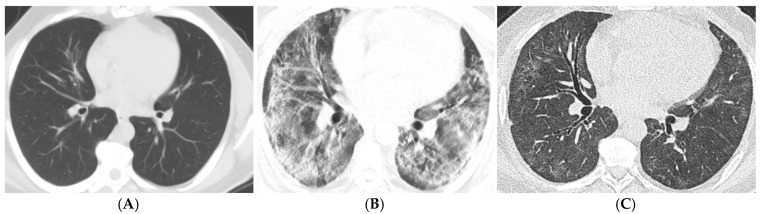

Background: This study aims to systematically evaluate the findings from computed tomography (CT) examinations conducted at least three months post-diagnosis of COVID-19 in patients diagnosed between 2020 and 2024. Objective: To determine the frequency and characteristics of CT findings in the post-COVID-19 period, analyze long-term effects on lung parenchyma, and contribute to the development of clinical follow-up and treatment strategies based on the collected data. Materials and Methods: Ethical approval was obtained for this retrospective study, and individual consent was waived. A total of 76 patients were included in the study, aged 18 and older, diagnosed with COVID-19 between March 2020 and November 2024, who underwent follow-up chest CT scans at 3-6 months, 6-12 months, and/or 12 months post-diagnosis. CT images were obtained in the supine position without contrast and evaluated by two experienced radiologists using a CT severity score (CT-SS) system, which quantifies lung involvement. Statistical analyses were performed using IBM SPSS 23.0, with significance set at p < 0.05. Results: The results indicated a mean CT-SS of 10.58 ± 0.659. Significant associations were found between age, CT scores, and the necessity for intensive care or mechanical ventilation. The most common CT findings included ground-glass opacities, reticular patterns, and traction bronchiectasis, particularly increasing with age and over time. Conclusion: This study emphasizes the persistent alterations in lung parenchyma following COVID-19, highlighting the importance of continuous monitoring and tailored treatment strategies for affected patients to improve long-term outcomes.

Abstract Image